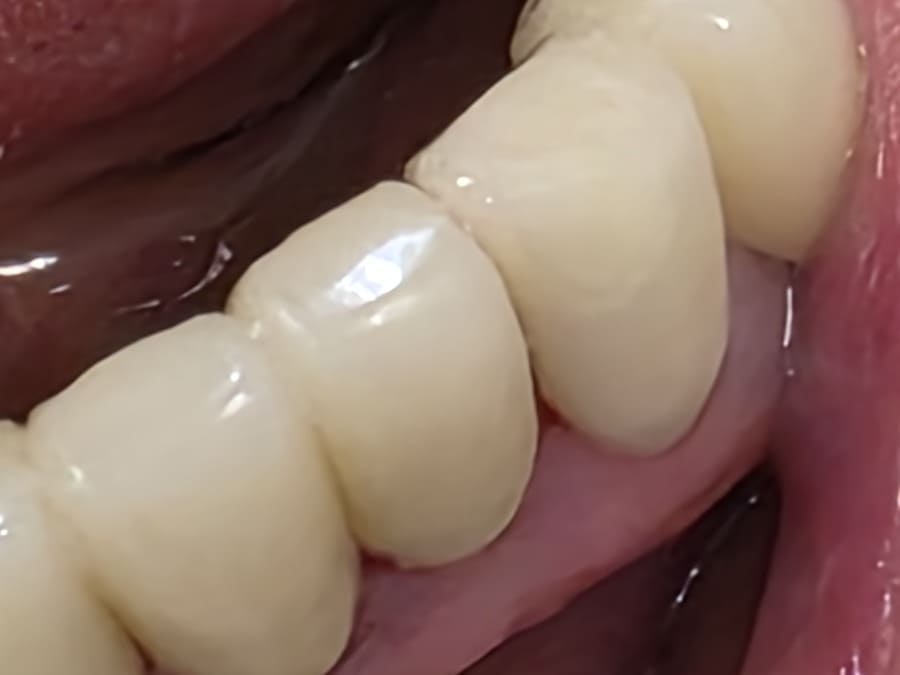

After

セラミッククラウン装着後